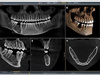

Radiologie Numérique

Le cabinet est entièrement équipé en radiologie numérique, permettant de réaliser des diagnostics plus précis et rapides.

Nous sommes équipés d’un Cône Beam (radiographie 3D) de toute dernière génération.

Il s’agit d’un dispositif permettant de réaliser un scanner beaucoup moins irradiant et spécialement dédié aux examens dentaires. En un seul cliché, il est possible de radiographier toute la bouche, de la reconstruire virtuellement en 3 dimensions (3D) et de naviguer millimètre par millimètre dans cet espace.

Il est l’examen de choix en implantologie, car il permet de visualiser les volumes osseux disponibles.